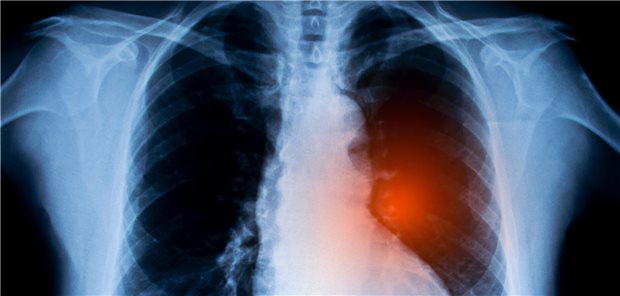

Systematisches Review und Metaanalyse

Krebs: Einsamkeit und soziale Isolation mit Gesamtsterblichkeit assoziiert